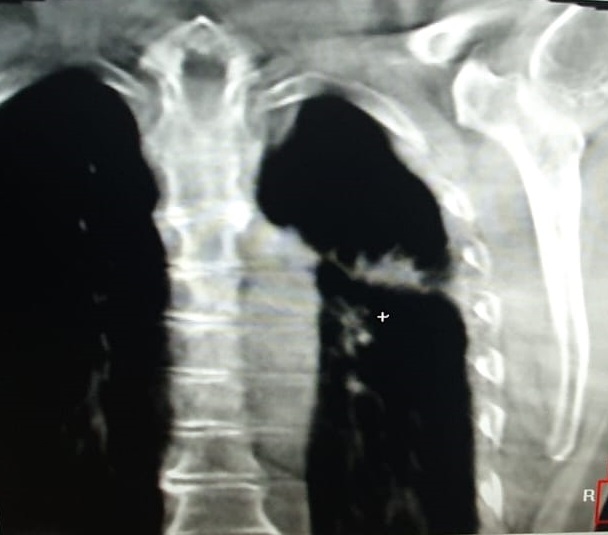

Pacientul M.L. in varsta de 56 ani, fumator de 40 ani, 20PA, s-a prezentat in clinica noastra pe data de 30.11.2022, cu diagnosticul de adenocarcinom pulmonar (neoplasm pulmonar) la nivelul lobului pulmonar superior stang, o tumora in stadiul IIIC, de dimensiuni mari T3, cu invazie ganglionara si mediastinala. Cazul a fost prezentat in Comisia Oncologica Multidisciplinara a clinicii noastre, unde s-a decis initierea tratamentului oncologic. Tumora fiind avansata loco-regional, era exclusa interventia chirurgicala in acest stadiu de boala (cancer pulmonar inoperabil).

Astfel, in perioada 5.12.2022 – 26.01.2023, pacientul a efectuat radioterapie externa cu fotoni, tehnica VMAT-CBCT, pana la doza totala DT = 66 GY/volum tinta formatiune tumorala pulmonara, un numar total de 33 fractii, concomitent cu administrarea saptamanala de polichimioterapie de radiosensibilizare, cu toleranta foarte buna.

Prezentam acest caz la scurt timp dupa finalizarea tratamentului (tratament cancer pulmonar), deoarece acesta este un caz fericit, la care s-a observat un raspuns aproape total chiar din timpul tratamentului RT, imaginile CBCT efectuate la inceputul, in timpul si la finalul tratamentului RT, pe care le atasam, aratand clar un raspuns extraordinar de bun la tratamentul efectuat.